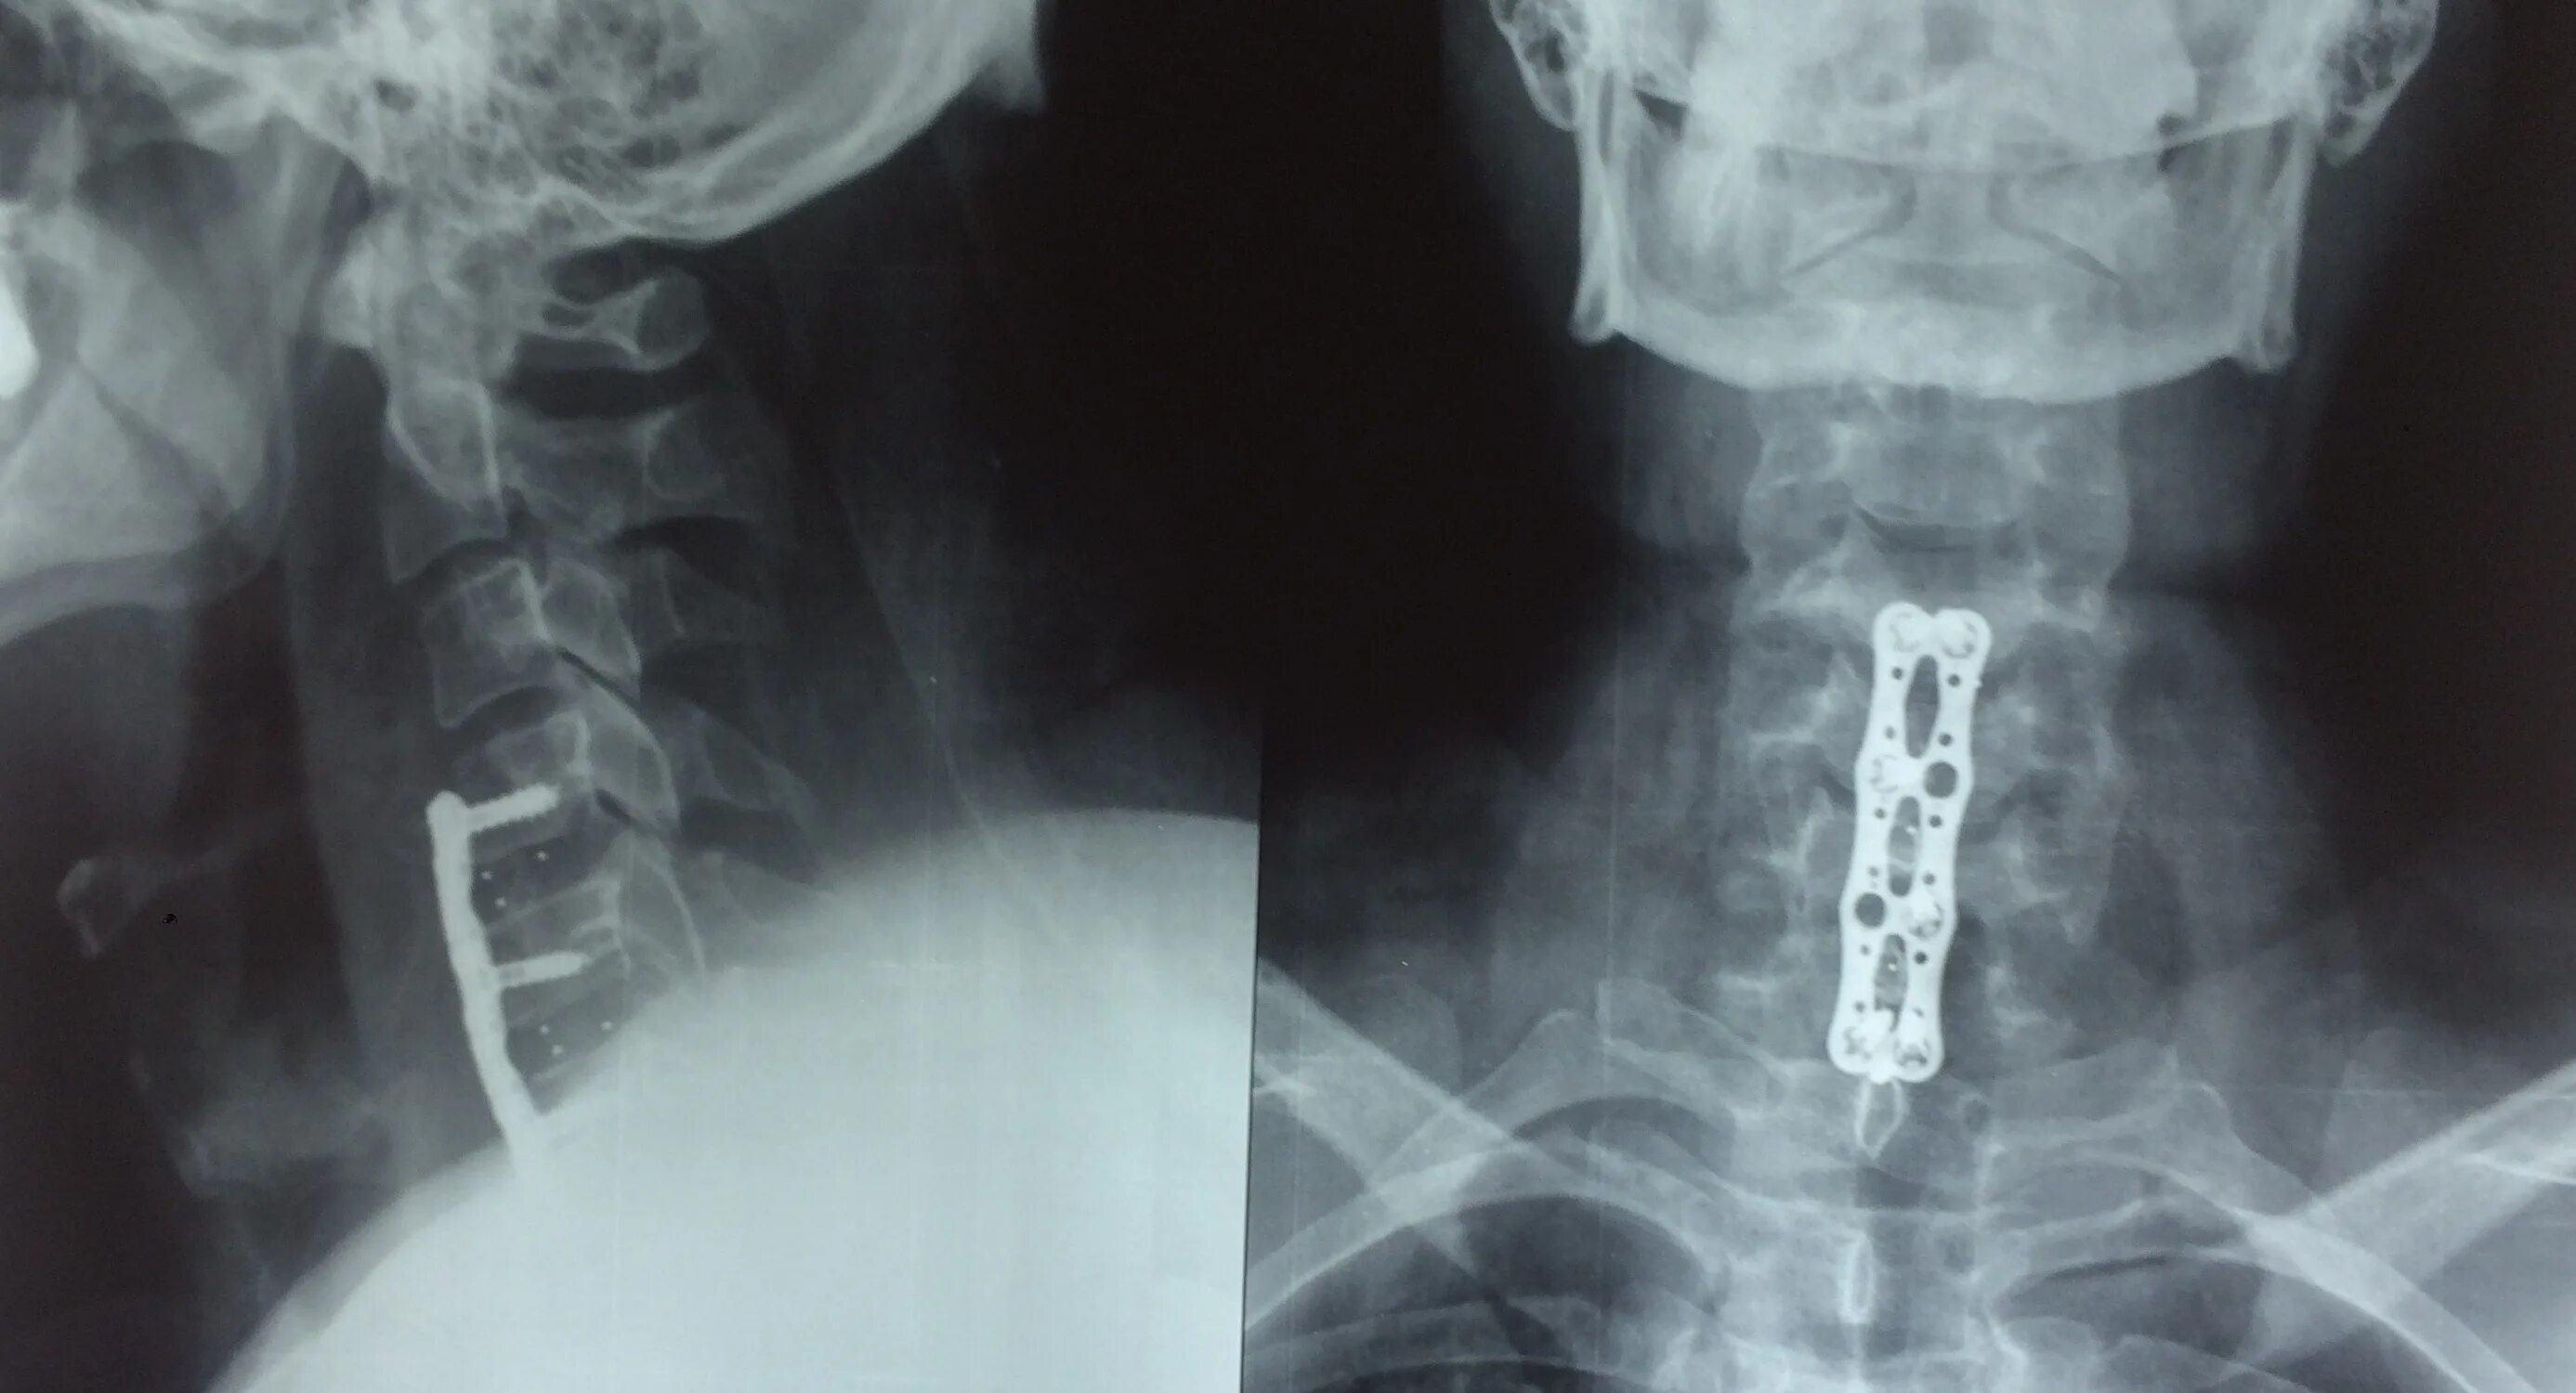

Операция на шейном отделе